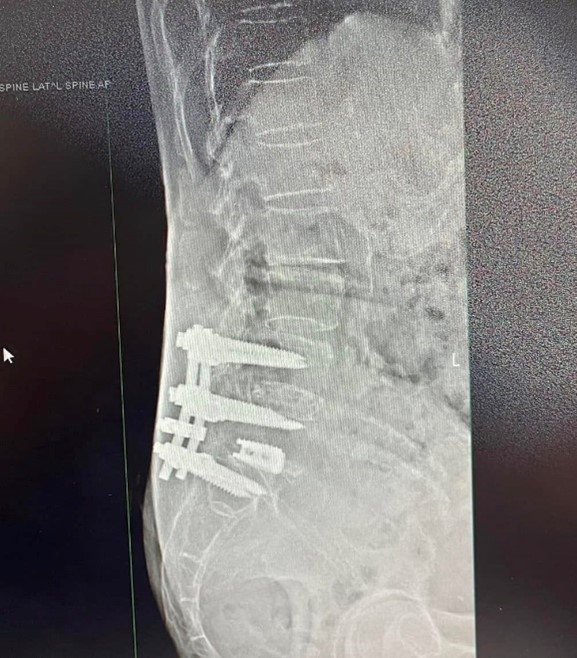

陳阿姨多年前曾接受腰椎手術(L4、L5、S1 節段植入鋼釘及人工椎間盤), 近期再度出現明顯疼痛。

近期影像顯示除既有手術節段外, 上方 L2–3、L3–4 節段亦出現椎間盤突出相關變化, 並伴隨神經症狀。